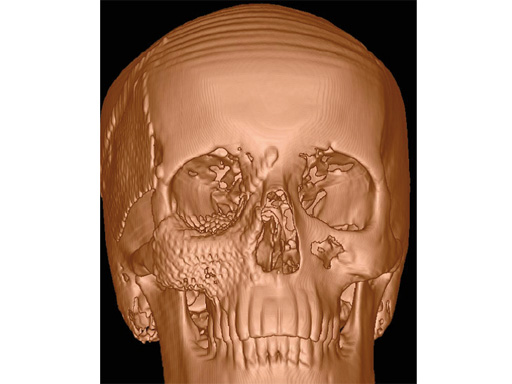

The new artificial sterilizable skull is the first autoclavable, one-piece human skull model intended for aiding initial plate contouring in the operating room, and for visualizing facial structures.

This sterile artificial skull model is an approximation of the average craniofacial anatomy, originating from data from up to 2000 analyzed CT scans. These scans were used to develop the matrix midface preformed orbital plates and the matrix mandible preformed reconstruction plates (Fig 2), launched in 2008 and 2009, respectively. The manufacturing material is polyphenylsulphone, which allows the skull to be steam sterilizable, reusable, cleanable, and biocompatible.

This new productthe sterile artificial skullcontributes to a more appropriate hard-tissue reconstruction in the CMF region, especially in cases of trauma, tumor, and craniofacial deformity. It provides a unique aid, always available and ready to use even in emergency cases.